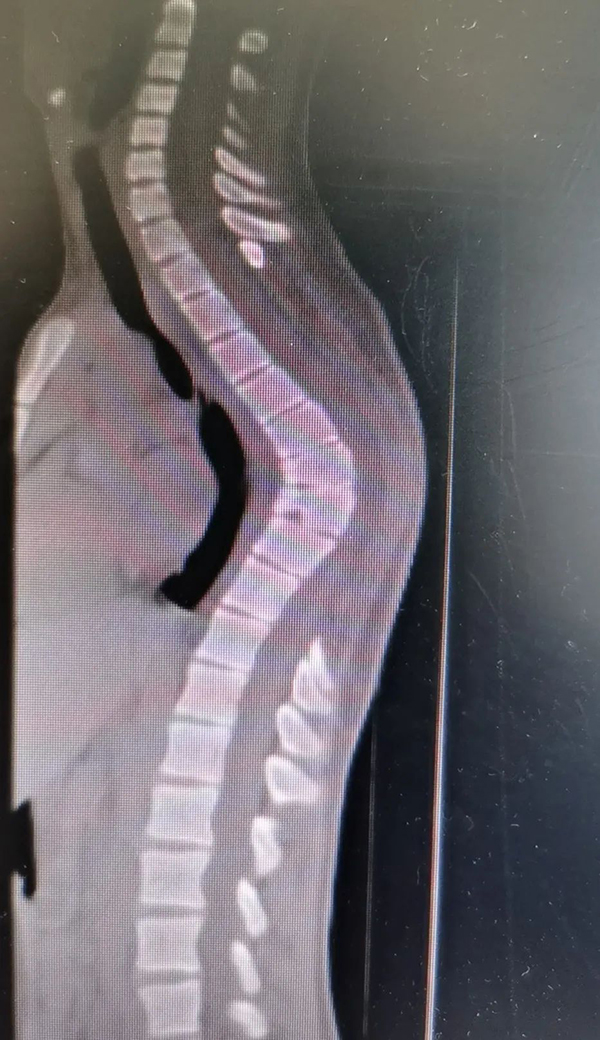

胸椎严重后凸图

图片尺寸821x547